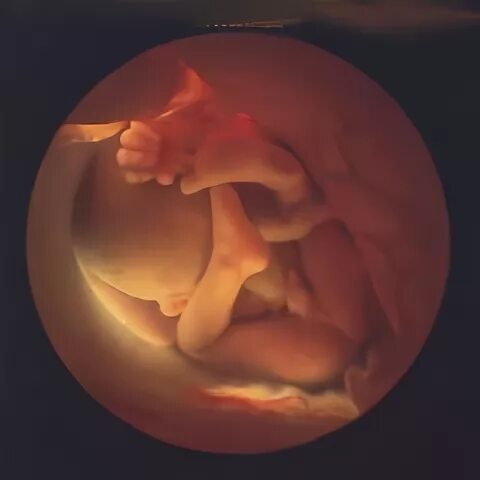

Плод 33